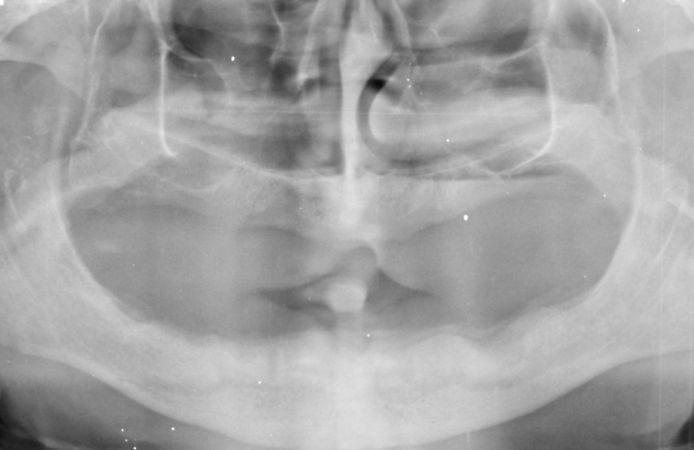

Figure 1.